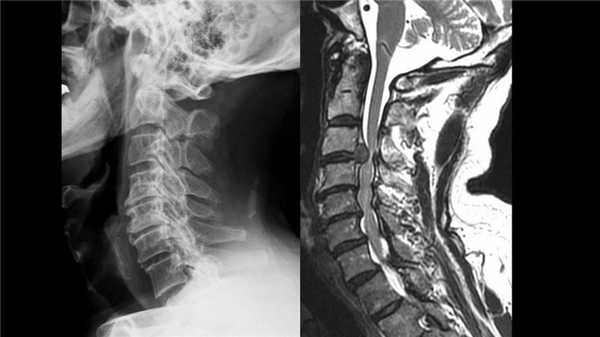

Грыжа шейного отдела на КТ.

Грыжа и клювовидные остеофиты, слева рентген, справа МРТ.